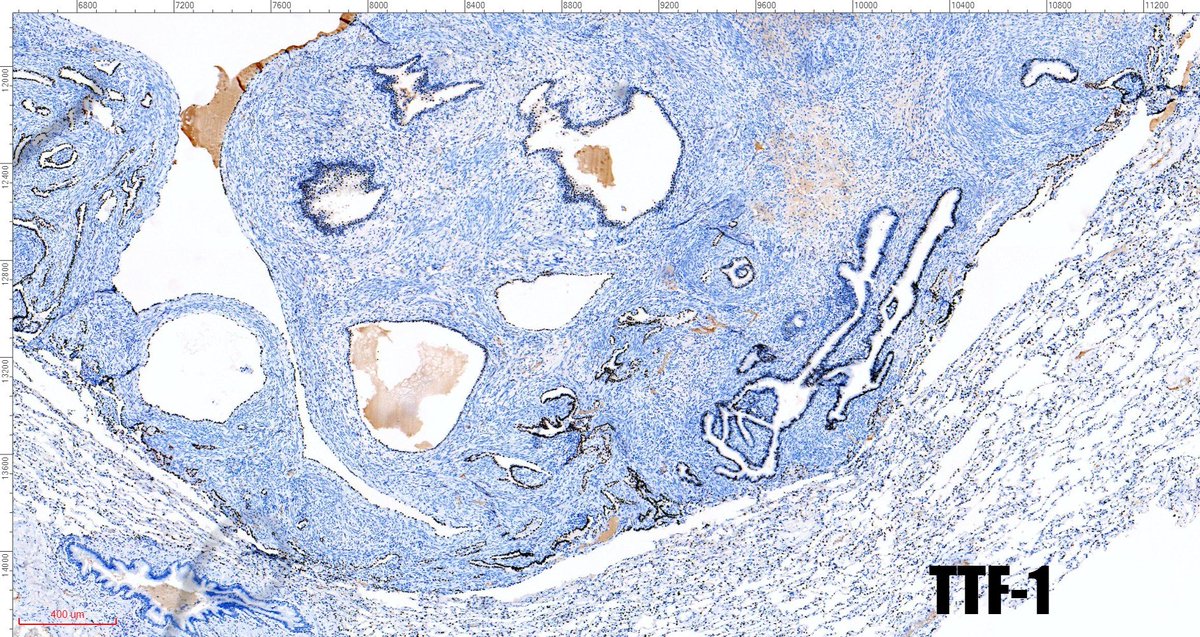

One of the most cryptic lesions for me in #pulmonarypath is the so called benign metastasizing leiomyoma. This case is a 37yo after myomectomy 3 years ago.

fabiotavora's tweet image. One of the most cryptic lesions for me in #pulmonarypath is the so called benign metastasizing leiomyoma. This case is a 37yo after myomectomy 3 years ago.